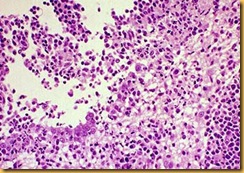

Unico metodo definitivo: esame istopatologico dei tessuti colpiti e conseguente indagine immuno-istochimica del tessuto.Esami sierologici: Gli anticorpi indotti dalla FIP sono indistinguibili da quelli indotti dal FeCV, forma gastro enterica molto più frequente. I portatori possono avere titolo basso o assente, gli animali con forma clinica in atto hanno di solito un alto titolo anticorpale mentre quelli con forme cliniche gravi possono essere avere tutti gli anticorpi legati ai virus e dare quindi titoli molto bassi. Gli anticorpi compaiono 7-10 gg. l'ingresso dell’agente eziologico. Il test è di scarsa utilità per il riconoscimento dei gatti portatori della forma enterica. Sono stati descritti casi in cui il titolo anticorpale IFAT è diminuito solo 25 mesi dopo che l'animale aveva smesso di espellere il virus. Vanno considerati positivi se il titolo è > 1.600 - 1:3.200 Metodica ELISA: ci sono test disponibili per uso ambulatoriale sono di tipo semiquantitativo: la positività equivale ad un titolo IFA >/= a 1:3.200. Esame virologico:Si può utilizzare l’immunofluorescenza diretta sul versamento o su un prelievo bioptico: non di semplice attuazione.